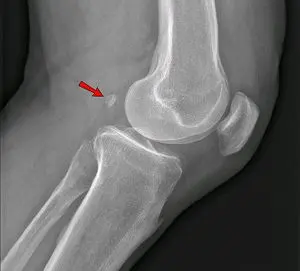

wat is de patella of de knieschijf

de knieschijf is het grootste sesambeen van het lichaam en bevind zich op het verloop van de eindpees

van wat hangt de grootte en vorm van de patella of knieschijf af

de grootte en vorm verschilt sterk naargelang de diersoort

welke specifieke kenmerken heeft de patella of de knieschijf bij de carnivoren

de patella heeft een spoelvorm

de basis is smaller dan de top

de benige knieschijf word proximaal en beiderzijds vergroot door een kraakbeenkap

hoe noemd dit bot

dit is de knieschijf of de patella

naar waar wijst het pijltje

naar de knieschijf of patella